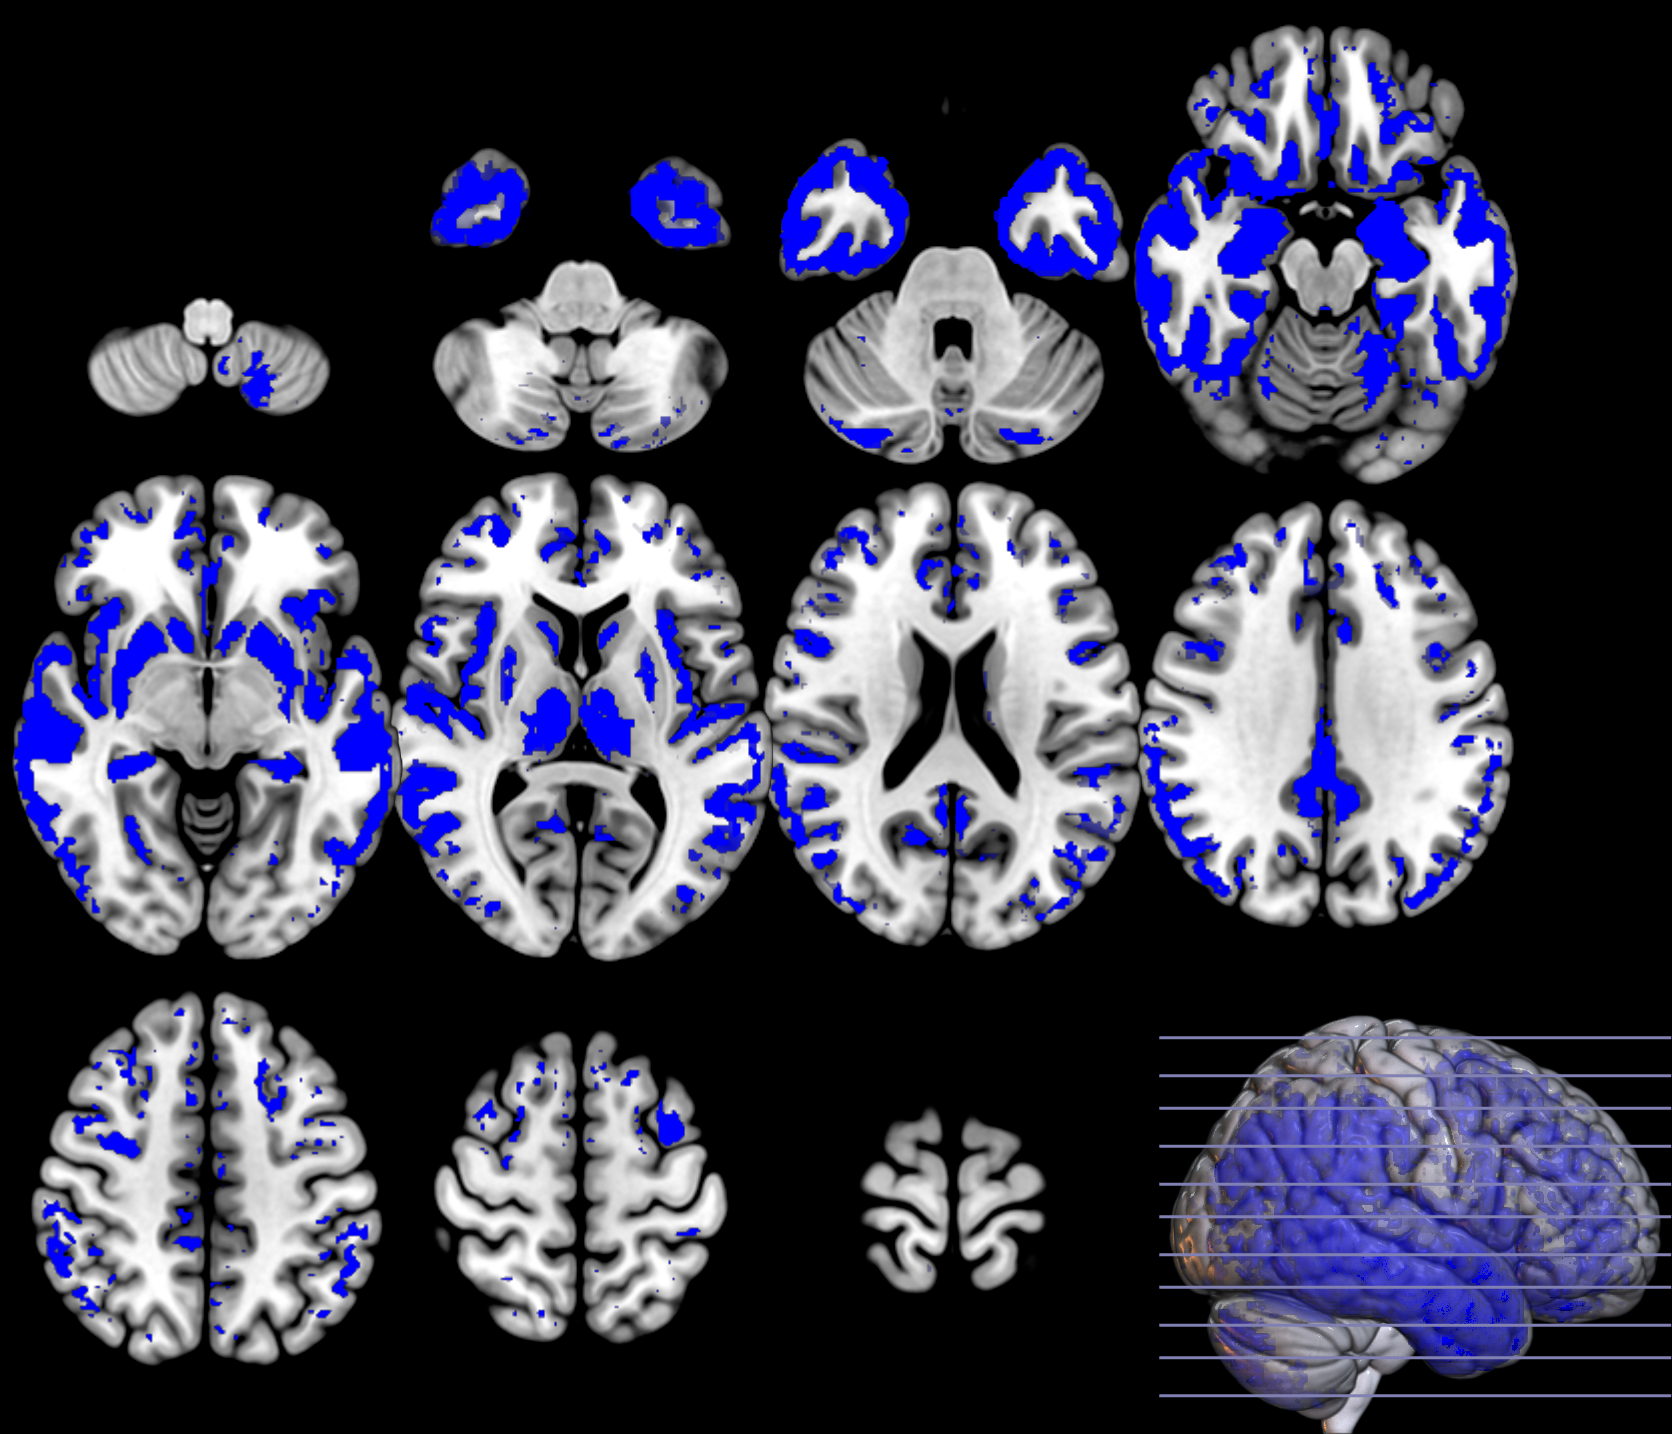

Based on the and values from the original dataset, and the ones obtained using a permutation analysis () for a selection of structures, e.g. hippocampus, we can compare the SPM with the previous inference approaches, as described in section 2.2.3. Note that in this paper the huge amount of voxels contained within an image limits the permutation analysis in this sense to some specific structures. Results on the hipocampus are depicted in figure 13. The permutation analysis reveals how the power of the approach is affected in this featured region, where a real effect might be found in almost the whole structure. The statistical power of the is preserved through the permutation procedure ( detected voxels vs voxels as shown in the same figure). It is also worth mentioning the CDF of the errors derived in the specific region and the distribution of the p-values within it. Recall that the dataset include advanced AD subjects thus the selected structure should be clearly affected by the disease.

To preliminary extend the analysis to the whole volume we approximately simulate the null distribution outside this featured region in two steps. First, we compute the set of p-values in the hippocampus (around voxels) following equation 16 and determine the T threshold that approximately provides the significance level, e.g. . Then, assuming that for any the probability of observation is , we threshold the rest of the image to obtain the significant voxels showing an effect. This approach clearly needs the multiple-comparison correction as several dependent or independent statistical tests are being performed simultaneously at the given significance level. Therefore, we decrease the significance level down to to avoid the presence of false positives in permutation analyses and then compare with SPM in the whole volume using the aforementioned configurations. In figure 13 we show the detection ability together with the control of type I error in the approach (map in red font). Note how the permutation test affects the detection ability of the classical CV approach (map in green font) and how the uncorrected voxelwise SPM approaches (in blue font ) tends to inflate false positives.